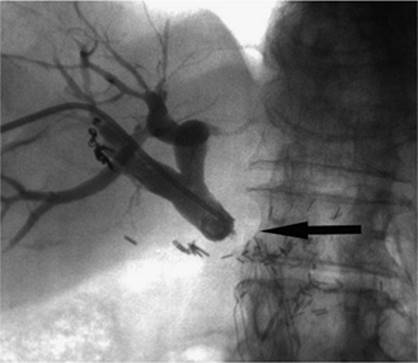

000431

Figure 35.14. Failed endoscopic placement of common bile duct (CBD) stent due to the presence of a large mass (black arrow) within the CBD. (Image courtesy of James Caridi, MD.)

000434

Figure 35.15. Successful percutaneous drainage using a left-sided biliary duct. Note that the drainage catheter has been advanced past the obstruction and into the small intestine. (Image courtesy of James Caridi, MD.)

000439

Figure 35.16. Patient presents with biliary obstruction. On hospital day 1, external drainage has been achieved using a right-sided bile duct approach. Cholangiogram shows complete obstruction in the mid common bile duct (CBD) (black arrow).

The indications for percutaneous biliary drainage include palliation of an unresectable primary or secondary malignancy of the liver causing biliary obstruction, benign strictures including biliary-enteric anastomosis as seen in liver transplant patients, sepsis secondary to biliary obstruction, preoperative decompression, stone removal, bile leak after laparoscopic cholecystectomy, biopsies, permanent internalization of drainage by placement of internal stent, and radiation therapy (29) (Figs. 35.18 and 35.19).

The only true contraindication to percutaneous biliary drainage is a bleeding diathesis. Usually this problem is overcome with the administration of blood products in the form of fresh frozen plasma, platelets, and vitamin K. Relative contraindications include the presence of sepsis, unless it is of biliary origin. The presence of ascites increases the risk of bleeding, and catheter misplacement, as well as making the procedure technically more difficult; hence ascitic fluid should be drained prior to performing the procedure. The presence of multiple intrahepatic obstructions also raises the risk of introducing bacteria to a bile duct that is not drained and that can rapidly become infected.

000443

Figure 35.17. On hospital day 2, internal/external drainage has been achieved by gaining access to the small intestine across the area of obstruction.

000250

Figure 35.18. This is the same patient as in Figures 35.16 and 35.17. A metallic self-expanding stent has been placed across the area of obstruction in the distal common bile duct. Note the waist in the stent (black arrow) due to the surrounding mass.

000446

Figure 35.19. Post–stent placement and balloon angioplasty. No residual stenosis is noted, and the stent is fully expanded.